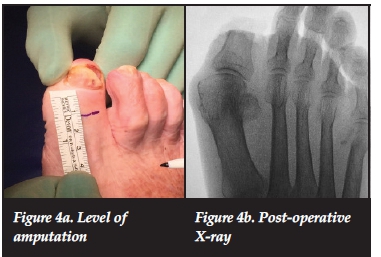

Once the case was discussed with an oncologist, informed consent was obtained from the patient to perform a partial amputation of the hallux. The hallux was amputated at the level of the mid-shaft of the proximal phalanx, allowing for at least a 15mm clear margin from the tumour edge (Figures 4a and 4b). The histology report once again confirmed the amelanotic melanoma, stage lib (Figure 5), with 20 mm clear margins. The patient was referred to the oncology unit for further treatment as required.